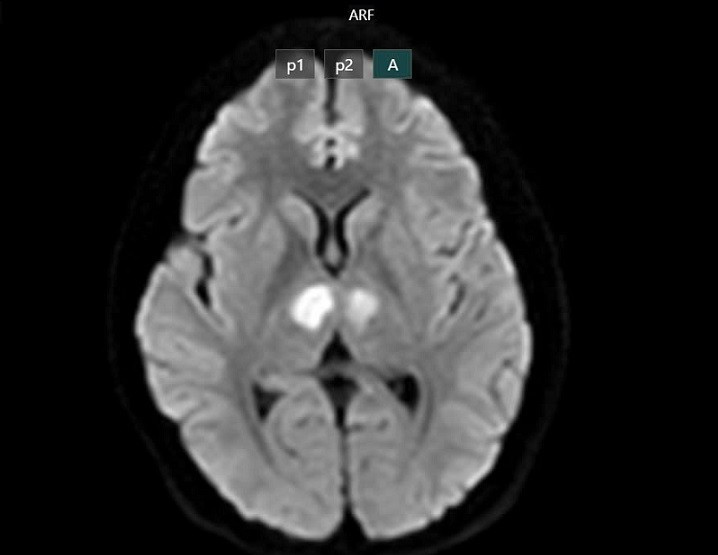

16h ngày 21/2 bệnh nhân vẫn nói chuyện với con, nhưng đến khoảng 19h30, gia đình phát hiện bệnh nhân trong trạng thái bất tỉnh, gọi hỏi không đáp ứng. Bệnh nhân không sốt, không co giật, không nôn. Người nhà đưa bệnh nhân đến bệnh viện tư để cấp cứu. Kết quả chụp MRI cho thấy não bệnh nhân có hình ảnh tổn thương vùng đồi thị hai bên. Gia đình xin chuyển bệnh nhân sang Bệnh viện Bạch Mai để được tiếp tục điều trị.

| Phim chụp cho thấy não bệnh nhân bị tổn thương vùng đồi thị hai bên. Ảnh BVCC |